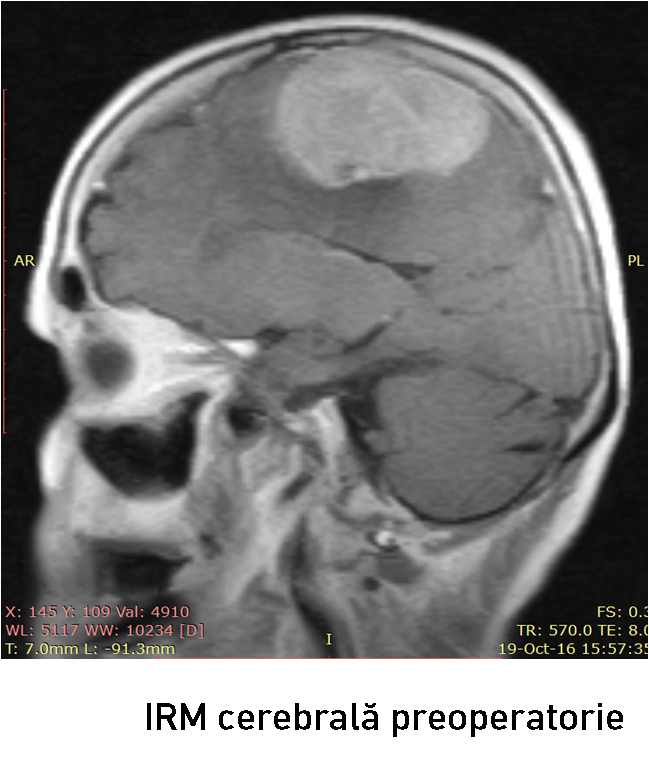

Examenul neuroimagistic prin IRM a stabilit prezența unei formațiuni tumorale intracraniene extraaxiale pe stânga (6

6 x 37 x 45 mm)la nivelul parasagital (1/3 medie a SSS) ce comprima regiunea precentrală și postcentrală stângă (fig. 1-2). Formațiunea de volum era atașată de sinusul sagital superior, de coasa creierului și capta intens substanța de contrast – suspect pentru un meningiom parasagital voluminos. Luând în considerație volumul leziunii tumorale, se impunea realizarea tratamentului neurochirurgical.